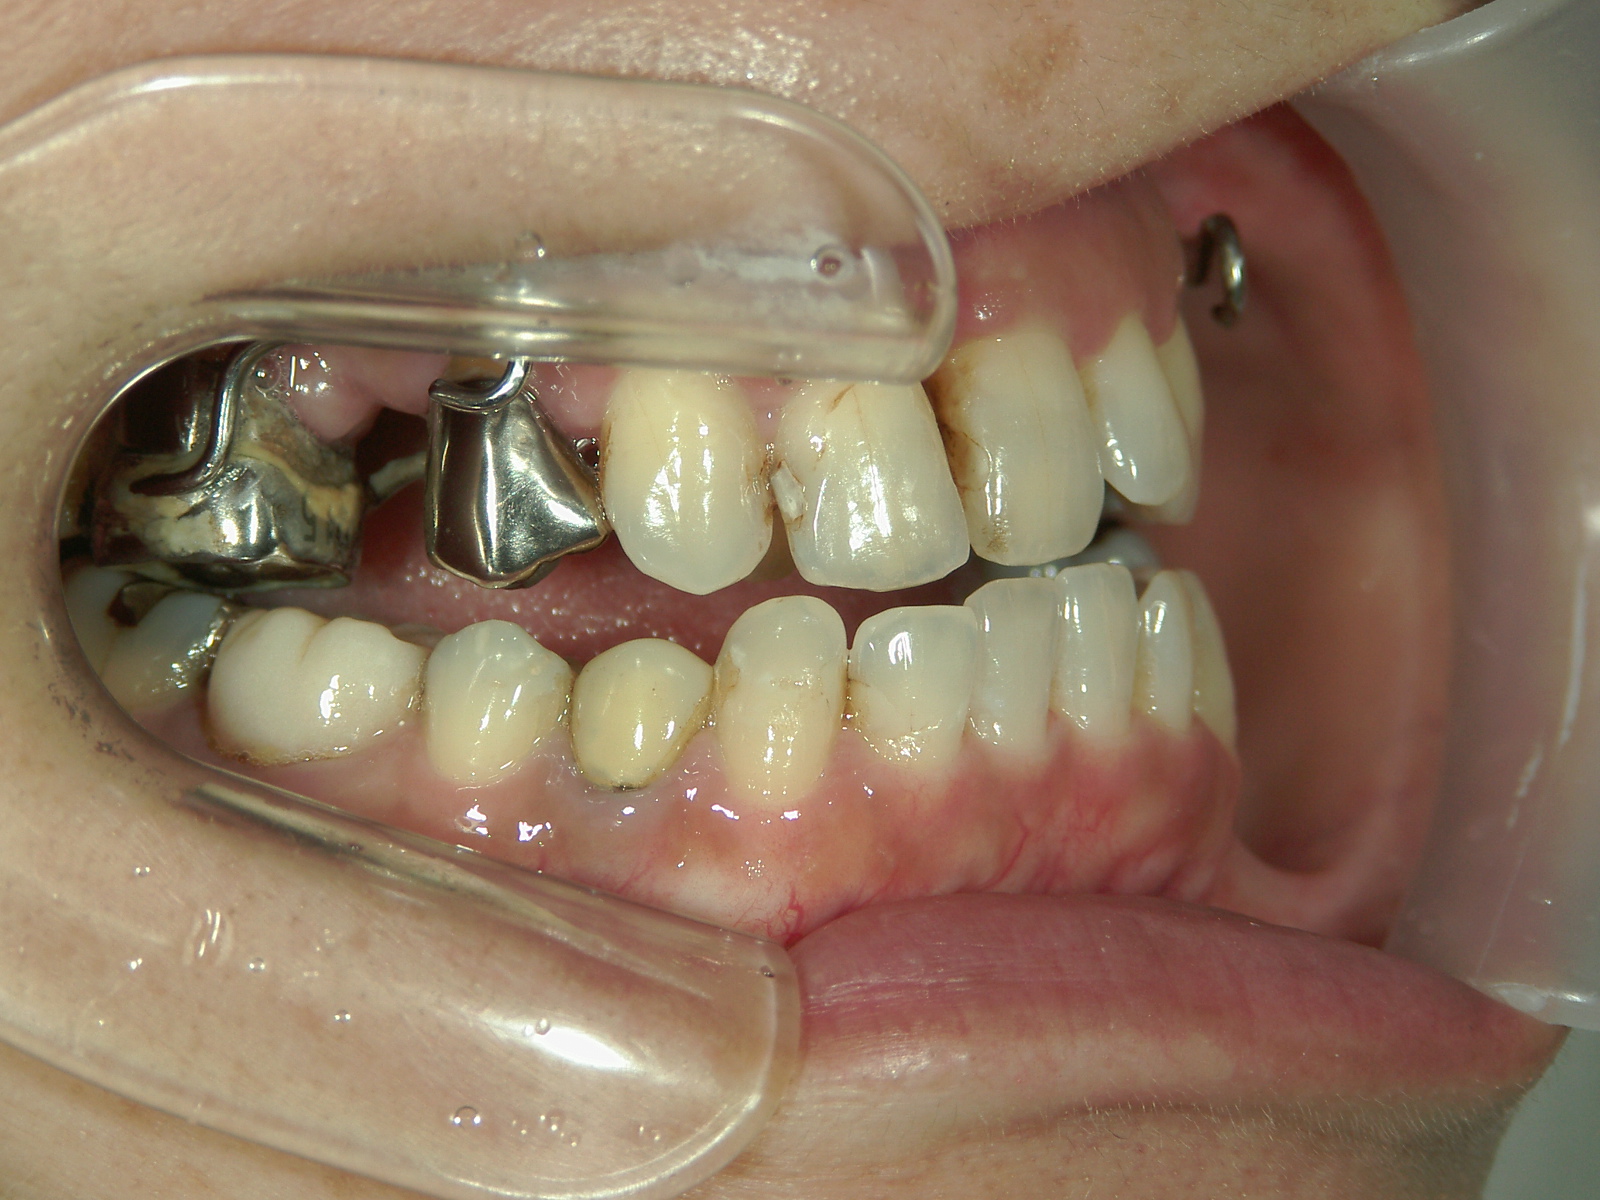

インビザライン矯正 症例(30)

主訴: 受け口、歯並びが気になる。

①患者様はインビザライン矯正をご希望でしたが、上顎骨が小さく、受け口になっているので、インビザライン矯正で治療するために「骨切断OPE」「矯正装置(MSE+フェイスマスク)」で上顎骨を拡大しました。

②右上前歯が内側に入っているため、歯列に入る隙間を作るためにワイヤー矯正を併用し、右上前歯を出しました。